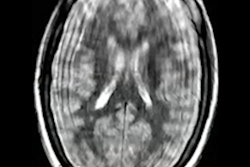

CT and radiography images of a 4-year-old girl with primary blast injury. CT images show multiple skull fractures (black arrows) in the cranium (a) and areas of pneumothorax (black arrow) and contusion (black star) in the left lung (b). (c,d) Radiographs of the same patient show left lower extremity and left hand fifth finger amputation, carpal bone fractures, and tissue defects. Image courtesy of Clinical Radiology.The mean age of the group was 9 years. Of the 74 patients, findings revealed 29 (39.2%) suffered primary blast injuries (PBIs), 32 (43.2%) had secondary blast injuries (SBIs), and 13 (17.6%) had complex blast injuries. Twenty-three (31.1%) were girls and 51 (68.9%) were boys. Radiography was performed in 32 (43.2%) patients and CT in 55 (74.3%).